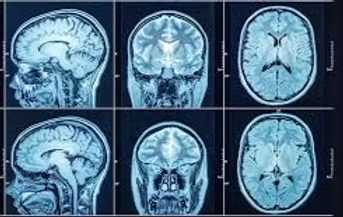

L'ictus cerebrale è una condizione clinica acuta dovuta al fatto che il flusso sanguigno in un'area del cervello e’ bloccato, o per un'improvvisa emorragia cerebrale.

Nel primo caso, chiamato ictus ischemico, il cervello non riceve ossigeno e nutrienti, quindi le cellule iniziano a morire entro pochi minuti.

Nel secondo caso, chiamato ictus emorragico, il sangue fuoriuscito esercita una pressione sulle cellule cerebrali, danneggiandole rapidamente.

La maggior parte degli ictus cerebrali sono di tipo ischemico (80%), e molto spesso si verificano quando coaguli di sangue ostruiscono i vasi sanguigni del cervello. Un ictus emorragico si verifica invece quando la parete di un'arteria cerebrale si rompe. L’ipertensione e gli aneurismi arteriosi – rigonfiamenti a forma di palloncino in un'arteria che possono rompersi – sono esempi di condizioni che possono causare un ictus emorragico.

Il cervello controlla i nostri movimenti, immagazzina i nostri ricordi ed è la fonte dei nostri pensieri e linguaggio, ma e’ anche responsabile per altre funzioni come la respirazione e la digestione. Affinche’ tutto cio’ si svolga correttamente, il cervello ha bisogno di un costante fusso di ossigeno e nutrienti che vengono forniti dai vasi sanguigni. Se qualcosa blocca il flusso sanguigno, le cellule cerebrali iniziano a morire nel giro di pochi minuti. Tutto cio’ clinicamente si manifestera’ come un ictus cerebrale.